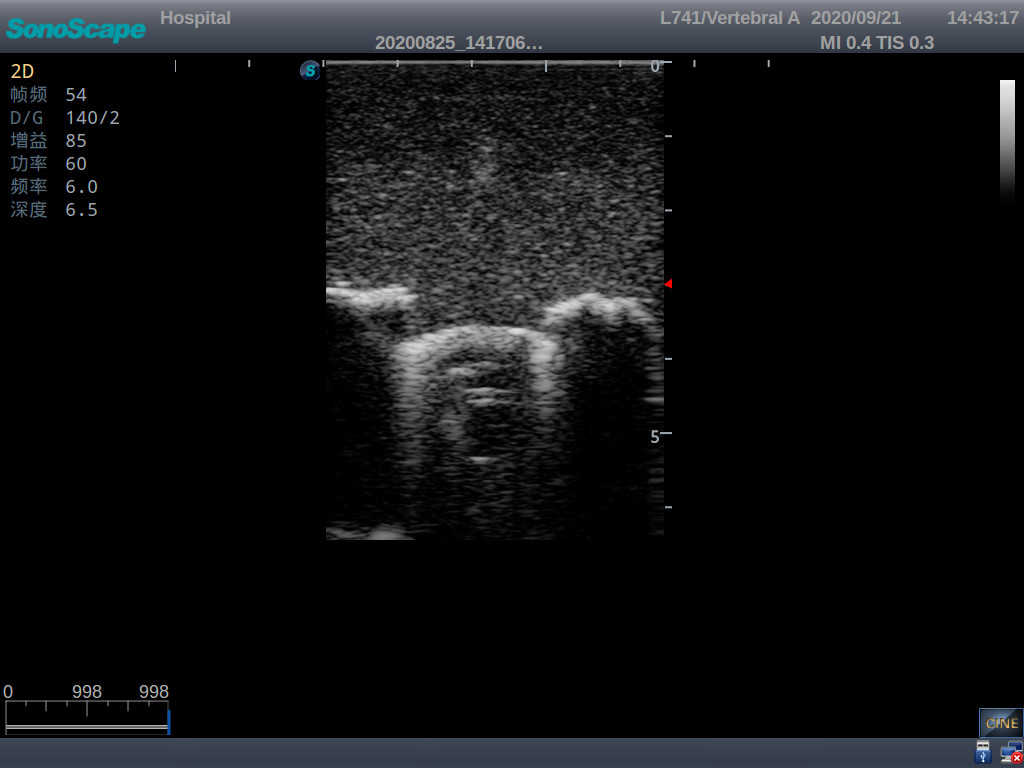

Model TYE1558.1

This model is an ideal choice for ultrasound-guided pediatric lumbar puncture training with true-to-life skin feel and touch, accurate anatomical structures as well as real clinical ultrasound images. Realistic resistance to needle tips and correct landmarks provide excellent hands-on experience.

2)  Real clinical ultrasound images